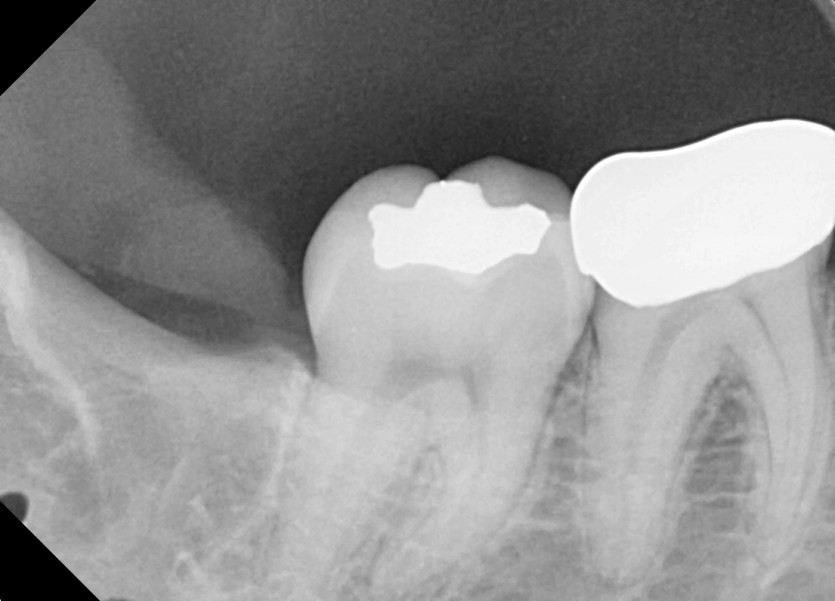

#18,28,38,48 사랑니 발치

구강 외과 전문의가 당일 발치했습니다.